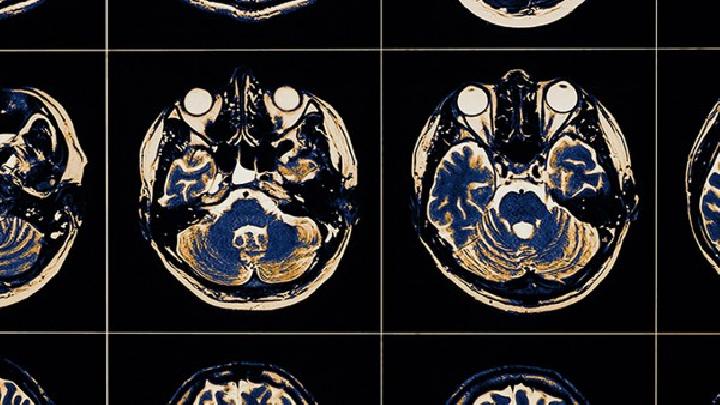

大脑萎缩是一种大脑疾病。大脑是控制人类思维、记忆甚至情绪的器官。如果大脑受到影响,会导致患者的思维能力、记忆力和情绪。